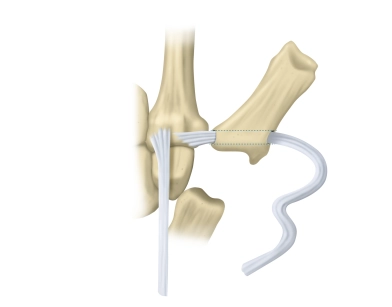

Eingriffe an Sehnen- und Sehnenscheiden

Entfernung eines Sehnenscheidenhygrom/Strecksehnensynovialektomie mit Retinakulumplastik